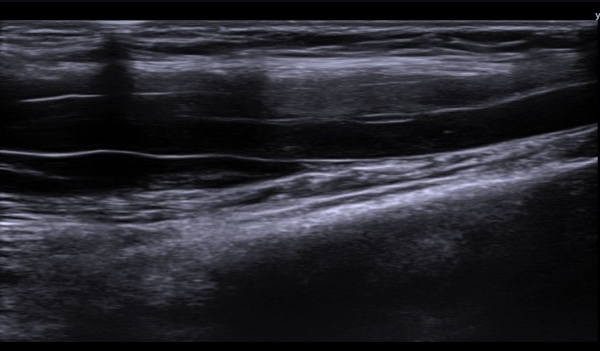

(»çÁø 1, 2). ŽÃËÀÚ¸¦ Á¶±Ù ´õ ±ÙÀ§ºÎ·Î À̵¿ÇÏ´Ï Á¤Á߽ŰæÀÇ Àú¿¡ÄÚ ºÎÁ¾ÀÌ °üÂûµÈ´Ù(»çÁø 3, 4).

Á¤Á߽Űæ Ⱦ´Ü¸é°Ë»ç¿¡¼­µµ Á¤Á߽ŰæÀÌ Àú¿¡ÄÚ ºÎÁ¾ÀÌ ±æ°Ô  °üÂûµÇ°í ½ÇÁú³» ƯÁ¤ ¼¶À¯¼ÒÀÇ

Àú¿¡ÄÚ ºÎÁ¾ÀÌ ¶Ñ·ÇÇÏ´Ù(»çÁø 5, 6).